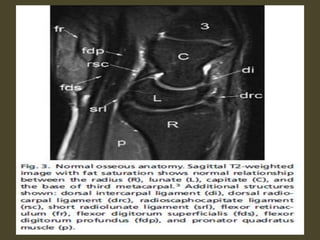

The transverse carpal ligament (short arrows) extends from the hook of the hamate (long

arrow) to the tubercle of the trapezium (arrowhead), forming the floor of the carpal tunnel.

At the radial aspect of the carpal tunnel, the flexor digitorum tendons are arranged in two

rows (separated by dotted line), the profundus tendons deep to the superficialis tendons. The

flexor pollicis longus tendon (star) is positioned at the ulnar aspect of the tunnel, separated

from the flexor carpi radialis tendon (curved arrow) by a ligamentous reflection of the

transverse carpal ligament. The median nerve is indicated (asterisk). - See more at:

http://radsource.us/palmar-bursae-and-flexor-tendon-sheaths/#sthash.mSFX1u0c.dpuf